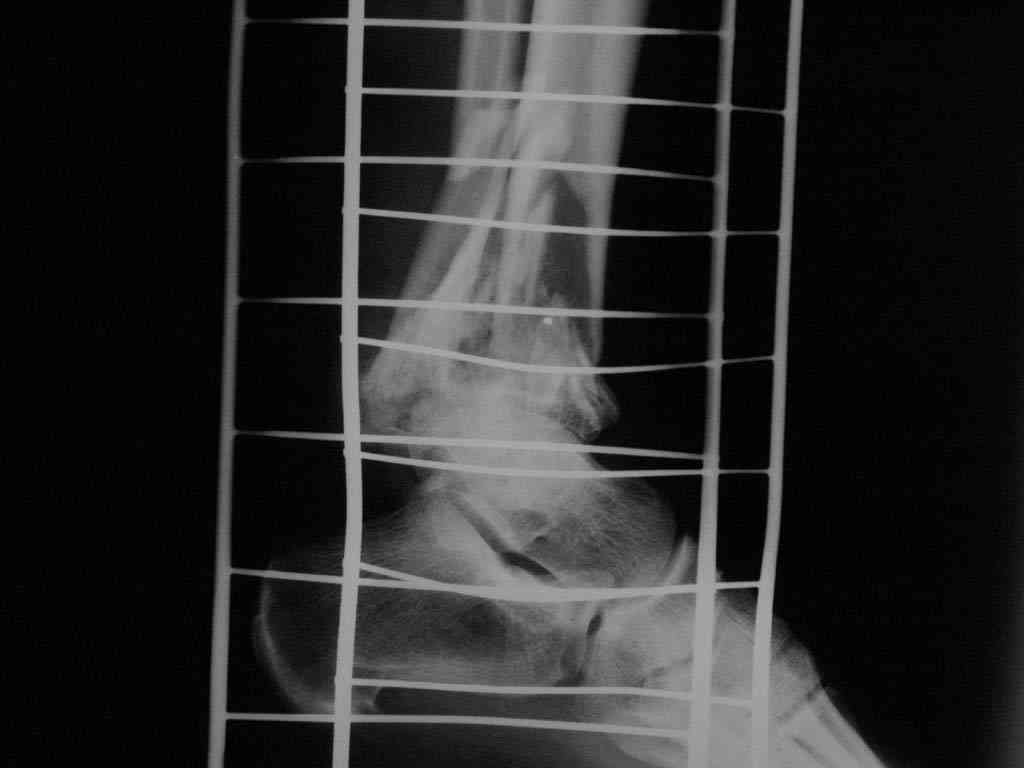

|  |  |  |  status localis на 14.11.08 (В ране визуализируется сухожилие.) | Больной А, 40 лет, находится в клинике с 15.10.08 с диагнозом: Сочетанная травма. Ушиб головного мозга лёгкой степени тяжести. Компрессионные переломы тел 12 грудного и 5 поясничного позвонков без неврологических осложнений. Закрытый внутрисуставной многооскольчатый перелом дистальных метаэпифизов обеих костей правой голени со смещением. Открытый внутрисуставной многооскольчатый перелом дистальных метаэпифизов обеих костей левой голени со смещением (см. Р-граммы). Хронический алкоголизм. Доставлен СМП после падения с 5-го этажа (не суицид). При поступлении состояние тяжелое. Глубокое оглушение. Дыхание самостоятельное, адекватное. Гемодинамика стабильная. По внутренней поверхности левой голени, в нижней трети, рвано-ушибленная рана 10-6 см, из раны выстоит проксимальный отломок большеберцовой кости, рана обильно загрязнена землёй. Интенсивная терапия в условиях реанимационного отделения, вытяжение за правую пяточную кость, параартериальная блокада обеих нижних конечностей, гипсовая лонгета на левую нижнюю конечность, ас-повязка на рану. Через 4 часа после поступления оперирован: после неоднократного промывания раны тёплой проточной водой с мылом, антисептиками, при ревизии определяется земля в канале проксимального отломка на глубину 3 см..., отсутствие надкостницы на концах дистального и проксимального отломков на 3 см. Удалено значительное количество мелких костных фрагментов, перемешанных с землёй, выполнена ПХО раны, резекция проксимального конца большеберцовой кости на 3,5 см, ЧКДО аппаратом Илизарова. Рана не ушивалась. В последующем перевязки раны с "Левомеколь", через 3 недели с момента травмы в ране определялись грануляции, нежизнеспособный конец дистального отломка. 10.11.08 ВХО раны, резекция дистального отломка на 3 см, перемонтаж аппарата наружной фиксации (см. Р-граммы). Отломки сближены на 2 см (остеотомию малоберцовой не делали). В настоящее время (5 сутки после операции) незначительное количество серозного отделяемого из раны, имеется дефект кости 4 см (см. Р-граммы). В последующем склоняемся к перемонтажу аппарата наружной фиксации, остеотомии малоберцовой кости в области повреждения, сближении отломков. По заживлению раны удлинение левой голени на 4 см. Однако, некоторыми высказывалось мнение о необходимости артродеза. Представляем рентгенограммы левой голени при поступлении, после повторного оперативного лечения и фото st.localis на 14.11.08. Будем очень благодарны за критику, комментарии, пожелания и мнения о дальнейшей тактике лечения.